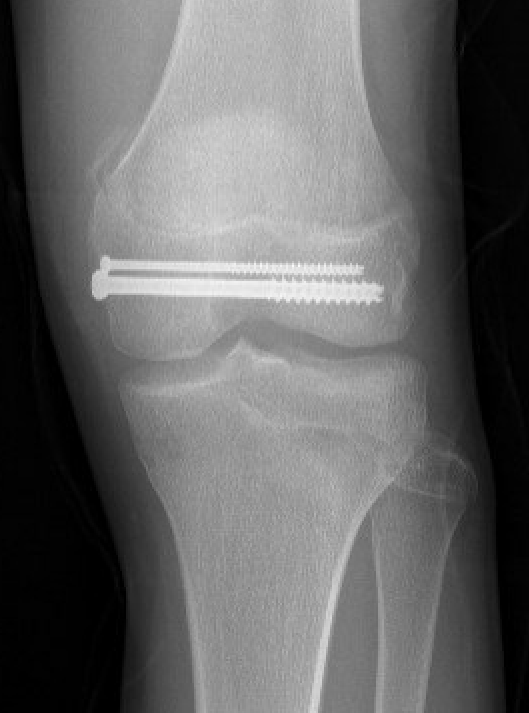

Salter Harris Type II with large Thurston Holland fragement

Technique

AO foundation screw fixation Salter Harris Type II

Reduction

- attempt closed

- may be periosteum blocked on tension / medial side

Medial subvastus approach to knee

- identify Thurston-Holland fragment

- physeal sparing metaphyseal screws